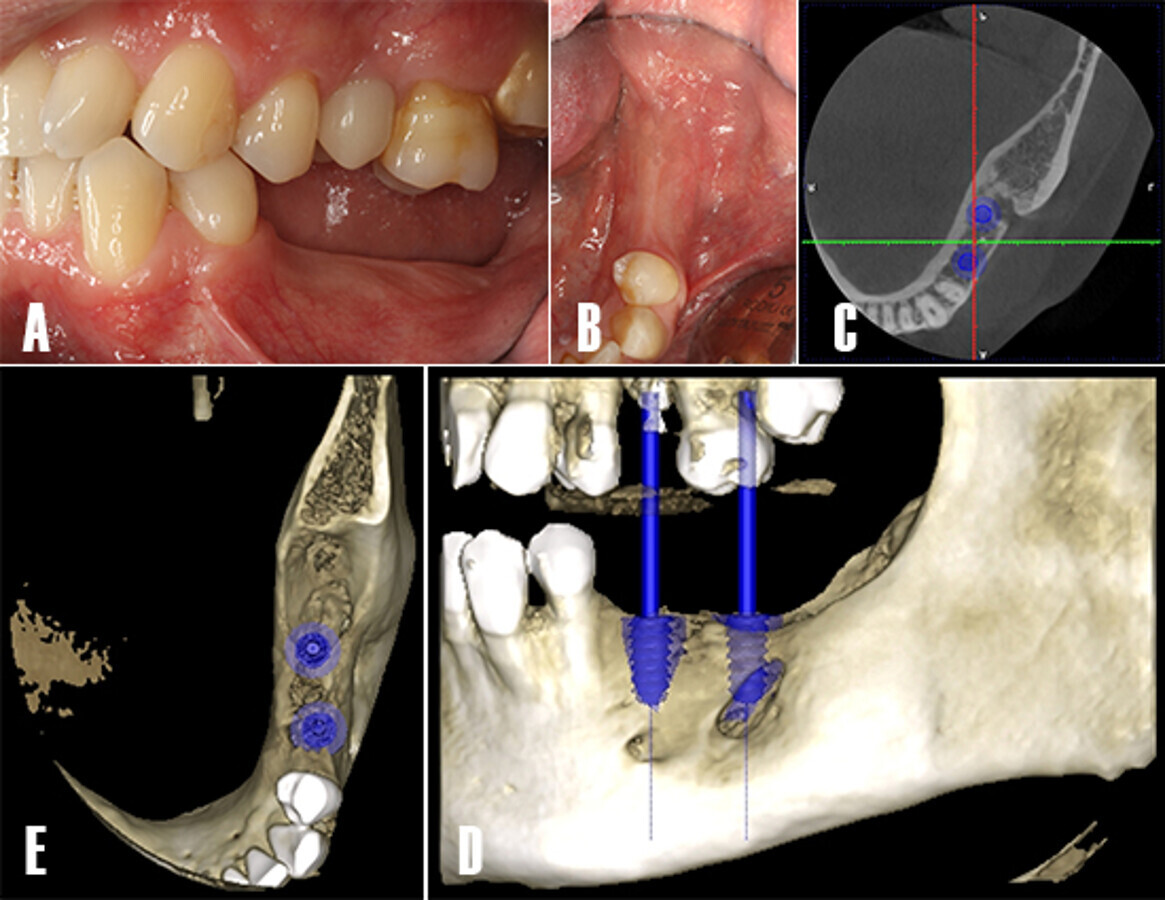

Figura 1. Fotografía intraoral. Imagen preoperatoria. Se observa el tercer cuadrante parcialmente dentado, nótese la ausencia clínica de los dientes 3.7 y 3.8

A la exploración clínica intraoral no se observaron alteraciones aparentes en suelo de boca, carrillos ni paladar blando. Los tejidos periodontales se observaron sanos y sin inflamación. Se observó ausencia de los dientes 3.6 y 3.7 (Fig. 1).

Se planificó la colocación de dos implantes mediante TCHC. Tras la evaluación tridimensional se observó un defecto óseo residual en distal del implante planificado en posición 3.7 (Fig. 11).

Figura 11. Planificación de implantes. Evaluación intraoral de la zona tratada. A) Se evalúa las necesidades protésicas y calidad de los tejidos blandos. B) En un vista oclusal, se observa los tejidos blandos saludables y presencia de mucosa queratinizada. C) Se realiza una TCHC y se planifica la colocación de dos implantes dentales en posición 3.5 y 3.7.

Dos implantes de 4.7 mm de diámetro y 11 mm de longitud fueron instalados (Phibo TSA®, Phibo Dental Solutions, Barcelona, Spain). El defecto residual en distal de 3.7 fue regenerado de forma simultánea con ß-fosfato tricálcico (KeraOs®, Keramat, A Coruña, Spain) (Fig. 12).